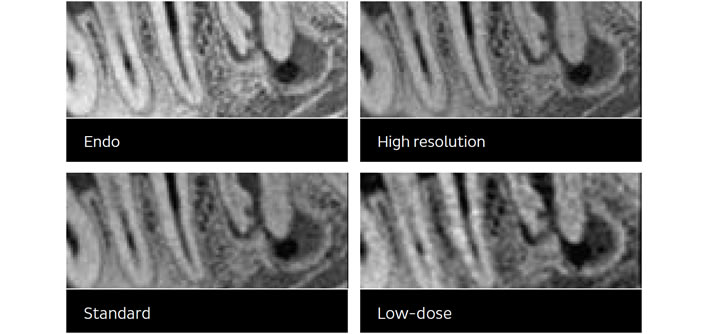

Uređaj koji mi koristimo ima mogućnosti snimanja u 4 rezolucije. Tako se količina zračenja može kontrolirati i smanjiti ovisno o indikaciji koju postavi Vaš doktor.